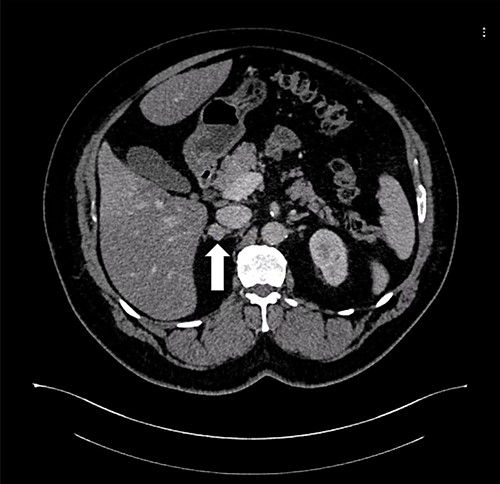

A 55-year-old male, with a BMI of 40, was referred to our surgical clinic at a governmental/academic hospital after being investigated at endocrinology department. His medical history was significant for insulin-dependent DM, uncontrolled HTN on four medications, chronic kidney disease and ischemic heart disease with multiple coronary stents on antiplatelets. A biochemical workup showed an elevated serum aldosterone of 100 ng/dl, elevated serum renin of 109 uIU/ml and elevated urinary ARR of >7000 mg/g. Serum potassium and sodium levels were within normal limits. A CECT of the abdomen and pelvis confirmed an isodense right adrenal focal lesion measuring 1.7 × 1.6 cm in pre-contrast phase, with enhancement on contrast phase followed by rapid washout, concluding a diagnosis of Conn’s syndrome (Fig. 2). Peri-operative optimization of blood pressure/cardiac status and management of anticoagulation were done through cardiac consultation. Due to his cardiac status, the patient was labeled as high risk for peri-operative cardiac events. A specialized cardiac anesthetist was consulted to perform the anesthesia.

Axial CT of the abdomen showing the right adrenal mass in Patient 2 (white arrow).